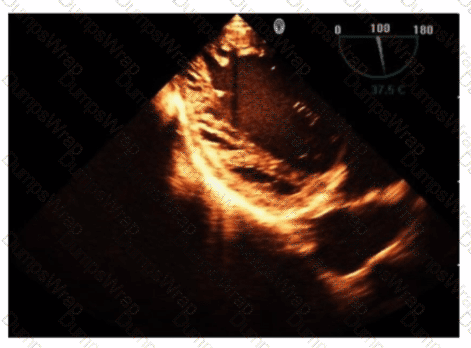

Which flow component is indicated by the arrows on this image?

Options:

Ventricular reversal

Diastolic flow reversal

Atrial reversal

Systolic forward flow

Answer:

CExplanation:

The Doppler waveform shows pulmonary vein flow with several components. The arrows point to small reversed flow spikes just after the atrial contraction wave, which corresponds to the atrial reversal (AR) flow component. Atrial reversal occurs as blood briefly flows backward into the pulmonary veins during atrial contraction.

Ventricular reversal is not typically seen in pulmonary veins. Diastolic flow reversal is abnormal and usually not part of normal pulmonary vein flow. Systolic forward flow is the major forward component during ventricular systole.

This interpretation is standard in ASE guidelines on diastolic function assessment and pulmonary vein Doppler evaluation【12:ASE Diastolic Function Guidelines†p.85-90】【16:Textbook of Clinical Echocardiography, 6e†p.130-135】.